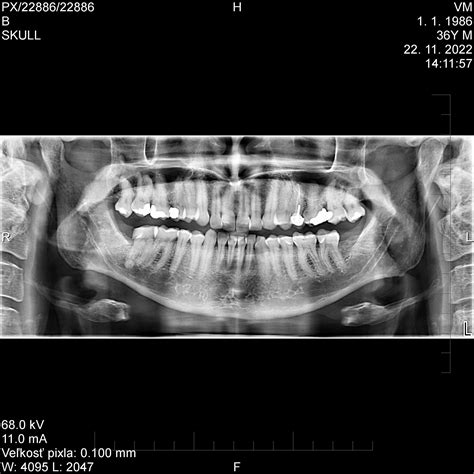

Veľmi často na bruxizmus upozorní práve zubný lekár v rámci preventívnych vyšetrení, a to u detí i dospelých. Všimne si opotrebovanú zubnú sklovinu, zlomené či vylomené zuby, poškodené korunky či plomby alebo tiež zväčšené svaly čeľuste.

Diagnostika bruxizmu zvyčajne prebieha na základe klinických príznakov a vyšetrenia chrupu zubným lekárom. V prípade, že existuje podozrenie na spánkové poruchy, lekár vás môže odporučiť k špecialistovi.